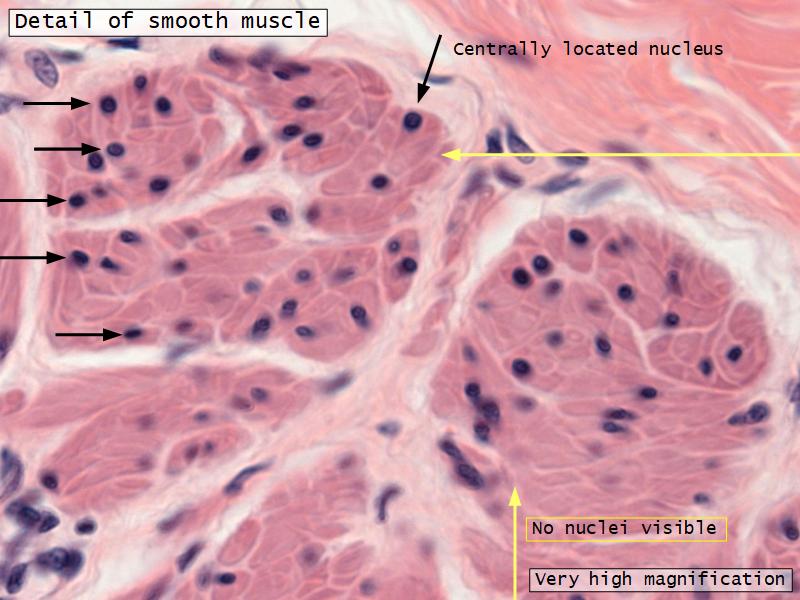

- Interlaced with smooth muscle fibres

- Smooth muscle

- Fibres and bundles